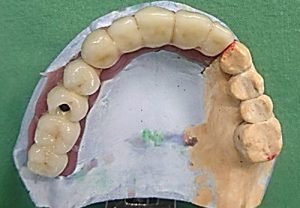

Prosthetic treatment in a toothless jawbone carried - 5 implants

2. PHASE - state before the provisional solution was made

3. PHASE - making a temporary solution

4.PHASE - implant placement

Prosthetic treatment in a toothless jawbone carried - 4 implants